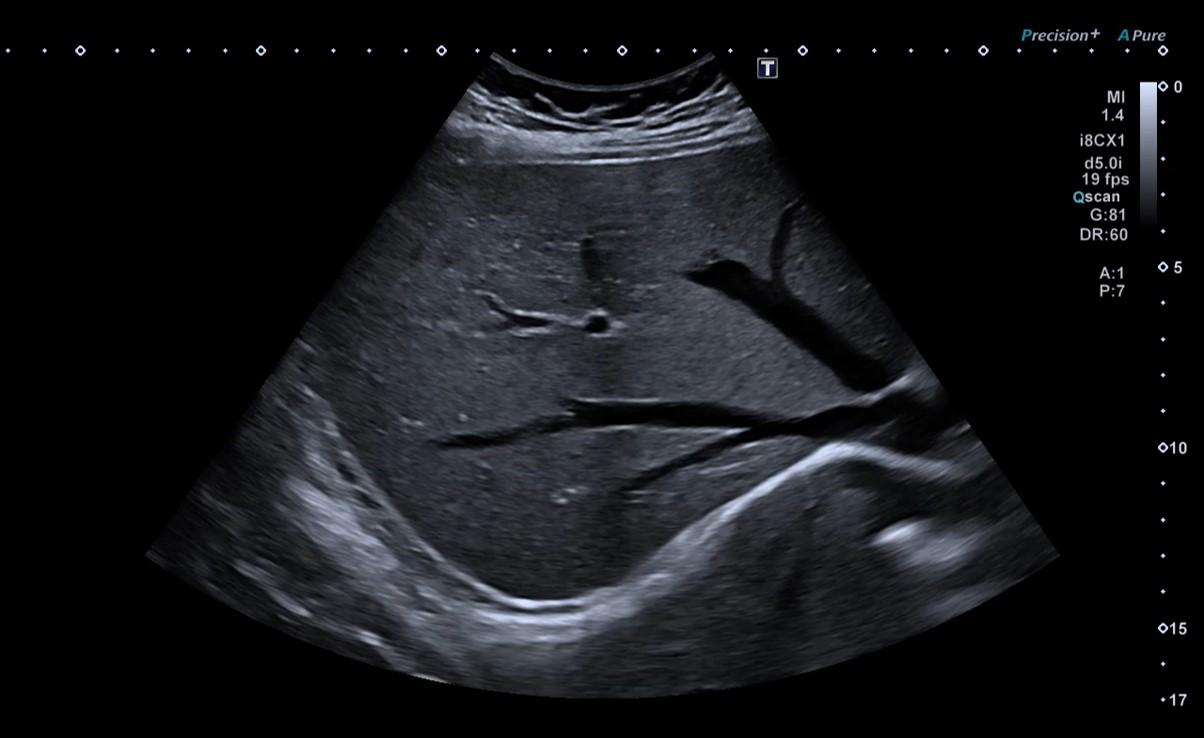

Renal and adrenal ultrasound uses high-frequency sound waves emitted by a probe, which pass through the tissues and are reflected, generating real-time images.

During the ultrasound, the patient lies on an examination table in a dimly lit room to improve image reading. The doctor applies a transparent gel to the skin of the abdomen and lower back, which facilitates the transmission of the sound waves and the movement of the probe.

The images are observed in real time on a screen and interpreted by the specialist doctor. The exam lasts on average between 15 and 30 minutes.

Renal and adrenal ultrasound allows a detailed study of the kidneys and adrenal glands, helping to identify various changes. It is possible to observe the presence of simple or complex cysts, nodules and solid masses in the kidney, as well as changes in the adrenal glands. This exam is also very useful for detecting kidney stones (renal lithiasis) and their complications, such as obstruction to the flow of urine. It also allows the detection of dilation of the urinary tract, a situation known as hydronephrosis, usually associated with blockages or stones. Structural changes compatible with infection or inflammation can also be identified.